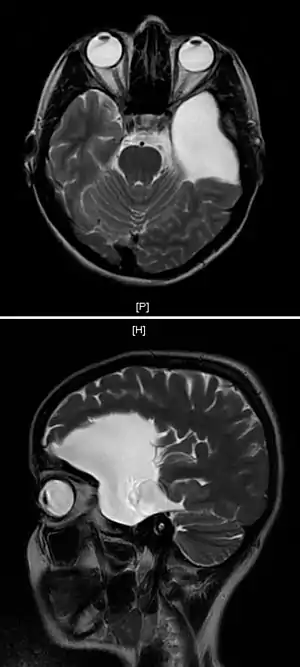

![]() | |

| An MRI of a 25-year-old woman with left frontotemporal arachnoid cyst. | |